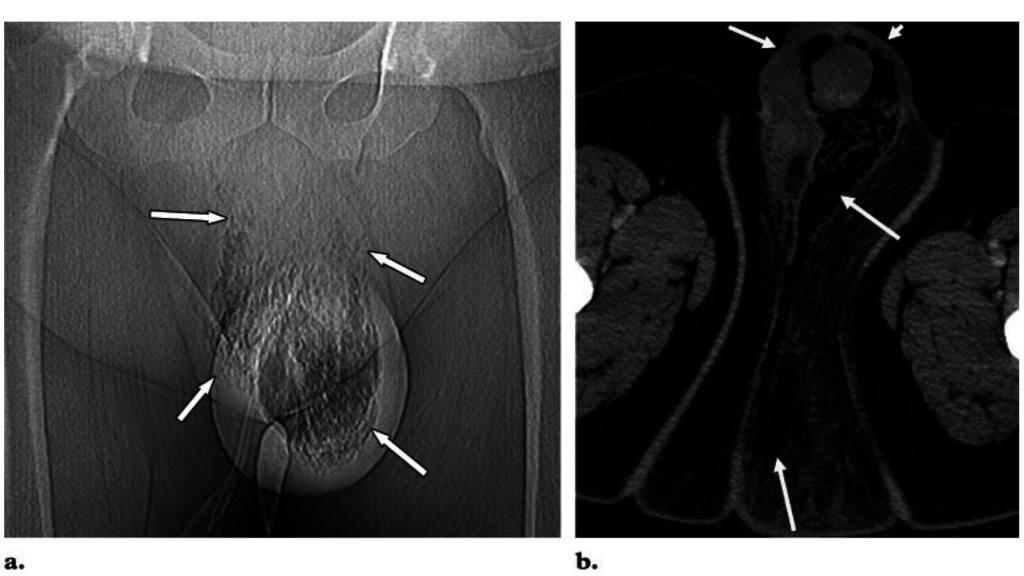

Radiografía de un paciente varón de gangrena de Fournier.

Radiografía de un paciente varón de gangrena de Fournier. BMJ Case Reports

Hay, sin embargo, una tipología específica de fascitis necrosante que ataca a los genitales: se denomina gangrena de Fournier, y se invita encarecidamente al lector a desactivar la búsqueda por imágenes si acude a Google para más información. El desafortunado protagonista del caso descrito en BMJ Case Reports es un ciudadano indio de 65 años que había sido tratado por un cáncer de tiroides. Como en otros incidentes de 'infecciones devoradoras', todo comenzó de forma relativamente inocua.

Para cuando se puso en manos de los urólogos, dos semanas después, la gangrena había causado estragos en su miembro: observaron que, aunque la parte interna del sistema urinario seguía en buen estado, se había producido en la práctica una sección con el aparato genital. Constataronuna autoamputación del falo, y tuvieron que recurrir a una penectomía total para retirar el tejido dañado restante y sanear la herida.

Los autores señalan que la gangrena de Fournier tiende a afectar al periné y el escroto, extendiéndose si se agrava al resto de la zona, pero que raramente se restringe como en este caso al pene. Se ha diagnosticado en otras lesiones por cateterismo, a causa de relaciones sexuales genitales y orales, y por la descerebrada práctica de aplicar cocaína al glande. También señalan que padecer Diabetes mellitus es un factor de riesgo, pero no era el caso de nuestro protagonista.